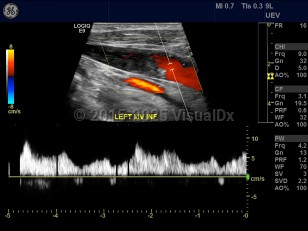

Internal jugular vein thrombosis

A serious event that is potentially fatal. Complications include pulmonary embolism and intracranial extension of the thrombus. Central venous catheters are a common underlying cause. May also result from intravenous drug abuse, head or neck infection, surgery, a localized malignancy, or even spontaneously. Clinical symptoms may be vague and subtle and can include fever, leukocytosis, swelling, and pain among others. May be a part of a superior vena cava syndrome, which is often associated with malignancy.